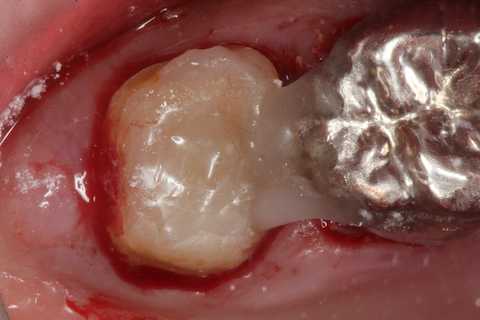

40代男性、左上7、歯根破折

今日は再建した歯を抜歯窩に挿入して固定するまで。

スーパーボンドとCRによる歯牙固定が良いと思う。

隣接歯の接着面には接着性を良くするためにグルーブを形成し、あらかじめスーパーボンドを流しておく。